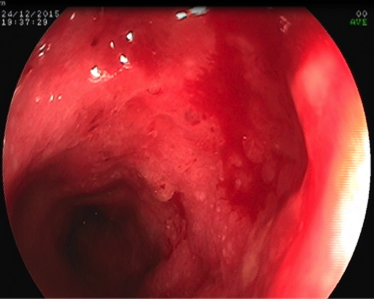

A 4-month-baby-girl presented with diarrhea of one-month duration. Her stools were loose, greenish and she used to defecate 4-5 times a day. In a week’s time, she was passing small amount of blood in stools, which was mixed with stool. She did not have fever, vomiting, dehydration or abdominal distension at the onset of symptoms. After 20 days of her illness, she was passing frank fresh red colored blood in stool. She was irritable, lethargic, pale and febrile. She was crying during passing the stool. She also developed pedal edema. She was first borne baby at term gestation from a non-consanguineous marriage and was exclusively breast-fed. Mother was ingesting milk products. Her pre-illness stooling pattern was normal. On the day of admission, her heart rate was 122/min, respiratory rate was 30/min and mean arterial blood pressure was 69 mm of mercury. She was lethargic, had pallor and pitting edema over feet. She did not have any rash, icterus, lymphadenopathy and petechiae, hepatomegaly, splenomegaly, perianal rash anal fissure or fistula. Her bowel sounds and per-rectal examination were normal. Her hemoglobin dropped from 11.2 to 9.5 g/dL. Her white blood cell count and platelets also decreased. C-reactive protein was raised. Fibrinogen was 211 mg/dL. Blood culture was sterile. Stool microscopic examination showed plenty of blood cells, pus cells. There were no parasites or fungal elements. Stool culture did not grow any pathogenic bacteria. Suspecting super-added sepsis and considering previous admissions at multiple hospitals, her antibiotics were upgraded to intravenous Meropenum and Fluconazole. She had hypo-proteinemia, hypo-albuminemia and electrolyte imbalance. Baby required packed red cell transfusion and albumin infusion. Clinically cow’s milk protein allergy, CMV colitis, immunodeficiency, very early onset inflammatory bowel disease (VEOIBD) and Clostridium difficile colitis were suspected. Colonoscopy showed entire colonic mucosa was erythematous, friable, ulcerated with complete loss of normal vascular markings and colonic haustral pattern. No pseudomembrane was seen. These findings were suggestive of pancolitis (Figure 1). Histo-pathological evaluation of mucosal biopsies revealed CMV colitis (CMV inclusion bodies). Tissue polymerase chain reaction (PCR) (qualitative) for CMV was positive. Blood PCR for CMV (qualitative) was also positive. CT enterography revealed normal small bowel. Mother’s IgG serology for CMV was positive. Babies IgM Serology was negative and IgG was 211 g/dL. The other systems like respiratory, central nervous system, eyes, hepato-biliary and bone marrow were unaffected. The child was treated with intravenous Ganciclovir (5 mg/ kg/ dose; 12 hourly) for 2 weeks and then oral Valganciclovir for 4 weeks. She stopped passing blood in stools after 7 days of Ganciclovir treatment. Her loose stools resolved in 10 days and after 2 weeks, she had complete resolution of symptoms. CMV DNA PCR was undetectable in the blood at 2 weeks, 6 weeks and 3 months of follow-up. Baby received total parental nutrition initially (7 days), followed by hypo-osmolar formula (from day 8 to day 14), and then term milk formula. The investigations for primary (B cells and T cell mediated) as well as secondary immunodeficiency (HIV serology) were normal. Cerebral spinal fluid analysis was not suggestive of meningitis. Stool toxin assays for Clostridium difficile were negative. At 6 months of follow-up, her stooling pattern was normal. She gained weight. Her albumin levels, and hemoglobin normalized. She was developmentally normal.

Figure 1a Entire colon had multiple deep ulcers.

Figure 1 Colonoscopy images showing pancolitis.

Figure 1b Mucosa was edematous and friable.